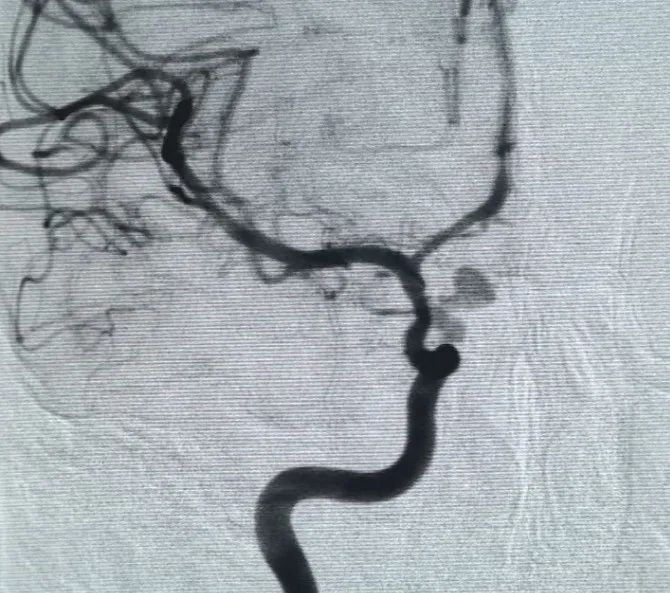

Un Perfiller®Bobine expansible de 3mm × 6 cm et un Perfiller®Une bobine expansible de 3mm x 2 cm a ensuite été placée pour compléter l'occlusion du cou. Par la suite, une Nuva®Le déviateur d'écoulement (TJED-D-5.0-16) a été livré et déployé à travers le col de l'anévrisme. L'angiographie de suivi dans les vues antéropostérieures et latérales a confirmé une excellente couverture, une bonne apposition de la paroi et une radiopacité claire, avec une stagnation marquée du contraste.

La procédure s'est déroulée sans complications et le patient s'est rétabli sans déficit neurologique.